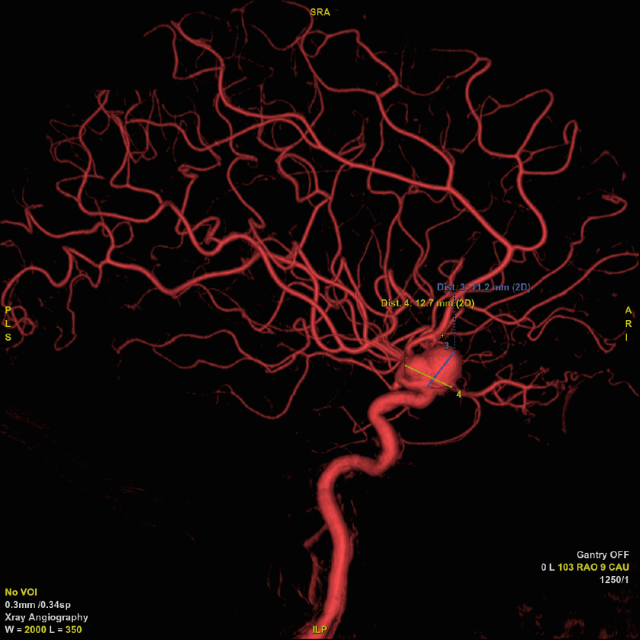

术中工作位造影。

3D-DSA重建结果。